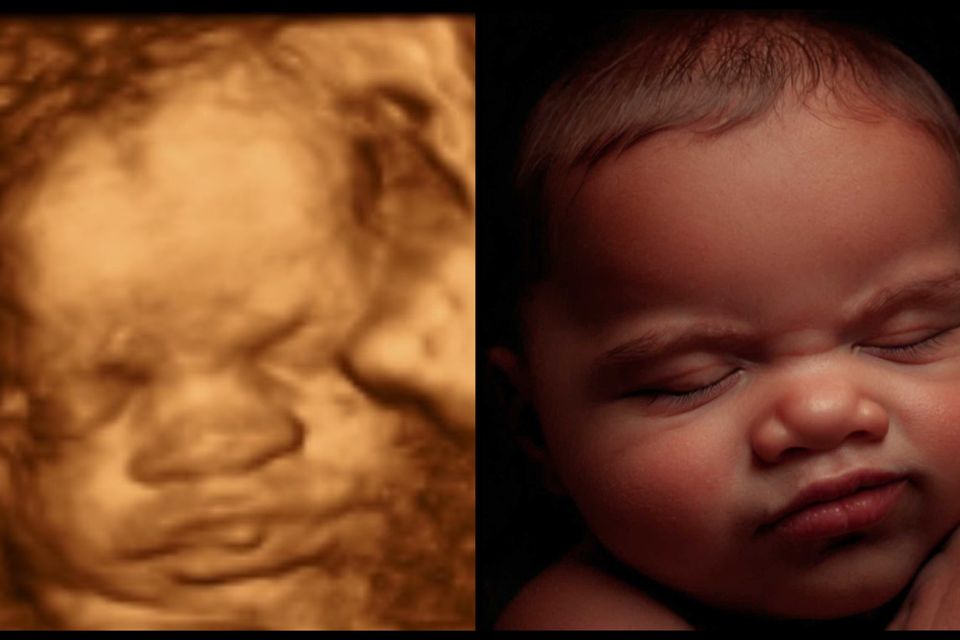

Most Realistic & lifelike photo you can get until the arrival of your little one. Using the newest technology to change your 3d/4d photo into something more realistic without changing any of your baby's features.